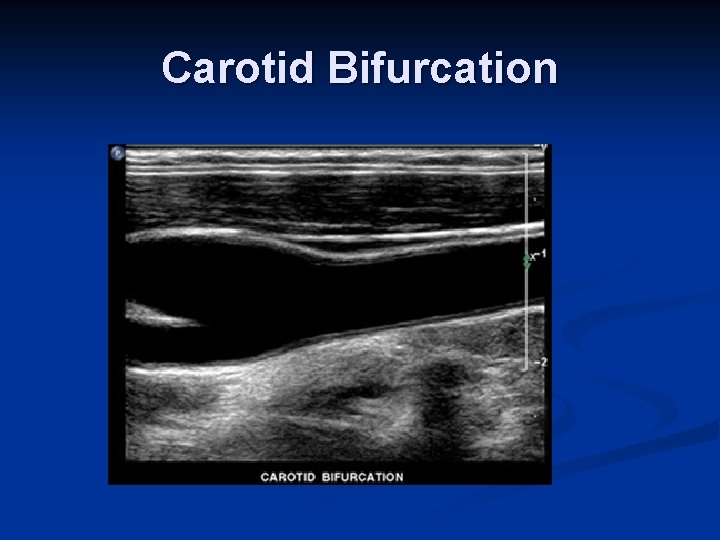

Carotid Bifurcation